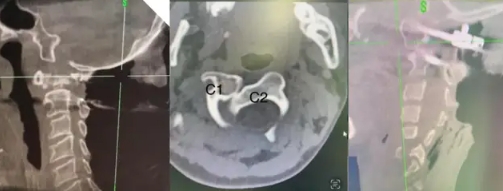

作为鼓楼医院脊柱外科颈椎专业组骨干成员,蒋军主任对颈椎相关疾患的诊治有深入研究和独到见解,除了常规的各种颈椎前后路手术方式以外,蒋主任还熟悉各种颈椎损伤及畸形矫形的复杂手术。对于寰枢椎这样以往被视为手术禁区的高难度手术,蒋主任同样颇多建树,在成人及儿童寰枢椎的骨折脱位手术方面,技术娴熟。众所周知,寰枢椎位于颈椎最上端,解剖结构复杂,周围有重要的神经和血管,该部位骨折脱位手术风险极高,对于手术操作空间有限的儿童患者,手术难度更加难以想象;蒋军主任凭借精准的操作和对解剖结构的深刻理解,已成功为众多患者解除病痛。

蒋军主任为一位患有Grisel综合征固定旋转半脱位的儿童患者成功完成后路寰枢椎侧块关节松解复位植骨融合内固定手术。